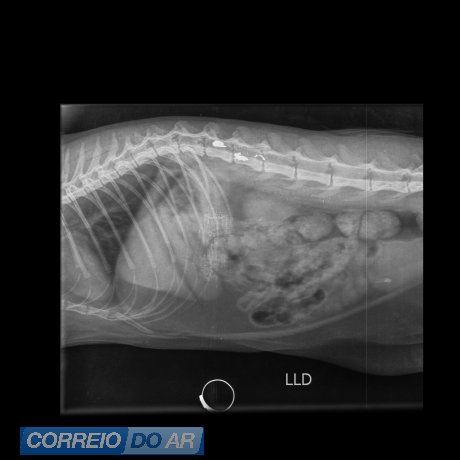

O animal apresentava um ferimento compatível com projétil. Não foi possível confirmar se o disparo partiu de arma de fogo ou de pressão. A gata foi socorrida e encaminhada para atendimento veterinário.